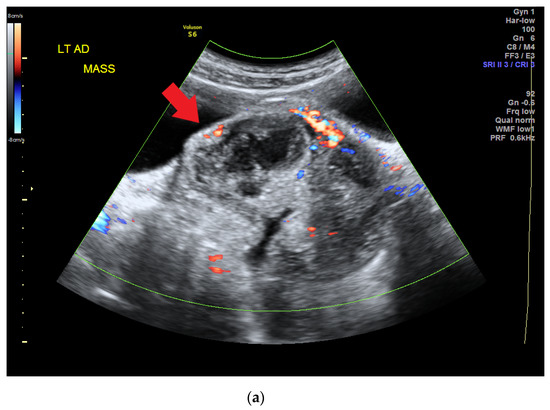

Frasier syndrome is a rare disease that affects the kidneys and genitalia. Patients who have Frasier syndrome develop nephrotic syndrome (NS) featuring focal segmental glomerulosclerosis (FSGS) that is resistant to steroid treatment in early childhood. Male patients can have female external genitalia (pseudo-hermaphroditism) [...] Read more.

Frasier syndrome is a rare disease that affects the kidneys and genitalia. Patients who have Frasier syndrome develop nephrotic syndrome (NS) featuring focal segmental glomerulosclerosis (FSGS) that is resistant to steroid treatment in early childhood. Male patients can have female external genitalia (pseudo-hermaphroditism) at birth and develop gonado-blastoma in their adolescence. Frasier syndrome is caused by mutations in the splice donor site at intron 9 of the Wilms’ tumor WT1 gene; these mutations result in an imbalanced ratio of WT1 protein isoforms and affect the development of the urogenital tract, podocyte function, and tumor suppression. Here, we report on a patient with long-term refractory NS who developed a malignant mixed germ cell tumor arising in a gonado-blastoma of the ovary 8 years after the onset of proteinuria. Full article